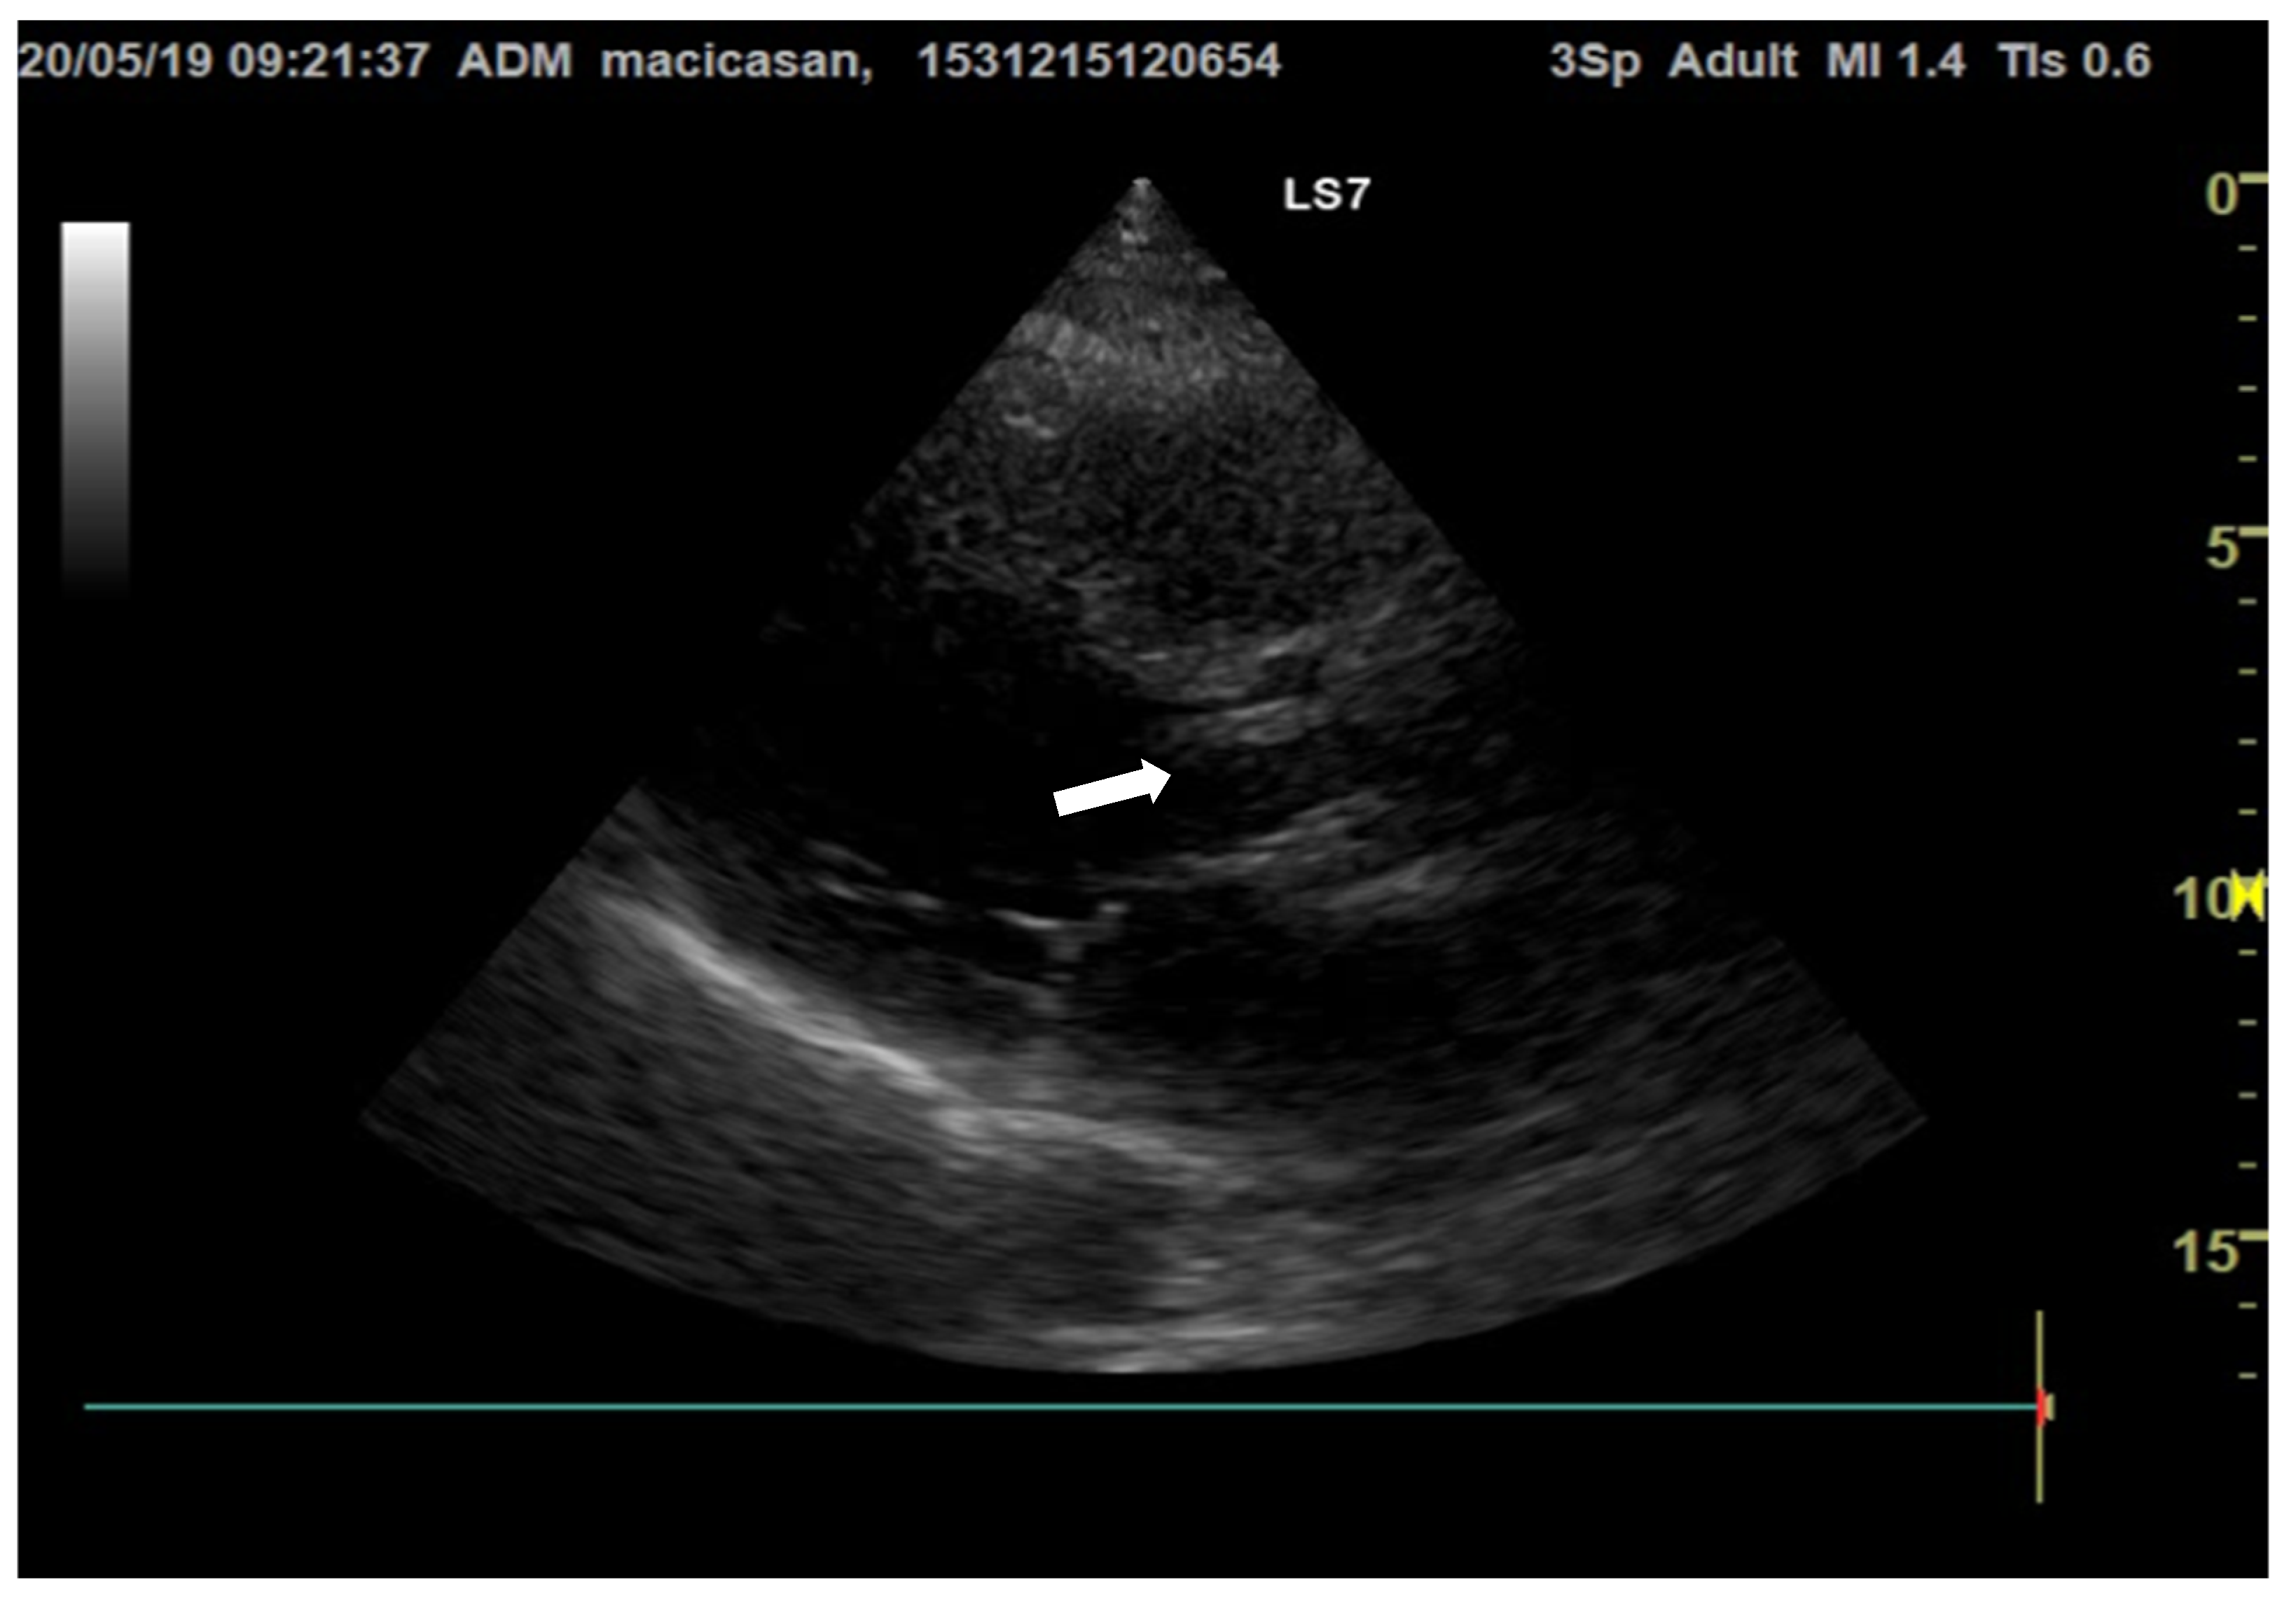

Doppler echocardiography showed a non-dilated left ventricle (LV—55/47 mm), grade III aortic insufficiency with a jet that hit the anterior mitral valve, mobile hyperechoic mass located on the aortic valve (3.5/0.95 cm) and on the tricuspid valve (2.5/1.4 cm), grade II tricuspid insufficiency, moderate secondary pulmonary hypertension (PAPs—50 mmHg), a slightly dilated right ventricle (40 mm sub tricuspid), TAPSE of 22 mm, EF of 50%, and free pericardium (Figure 2 and Figure 3).

Figure 3. Transthoracic echocardiography, long axis parasternal section, reveals hyperechogenic vegetations on the aortic valves (the white arrow is indicating the vegetation on the aortic valve).